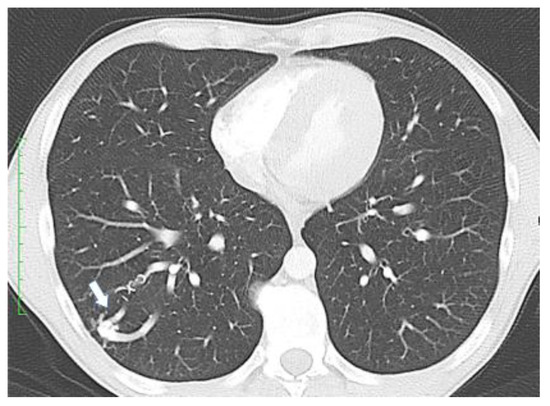

- Clinicians should screen all patients with a suspected or confirmed HHT diagnosis for pulmonary AVMs.

- Clinicians should use transthoracic contrast echocardiography as the initial screening test for pulmonary AVMs.

- Clinicians should treat pulmonary AVMs with transcatheter embolotherapy.